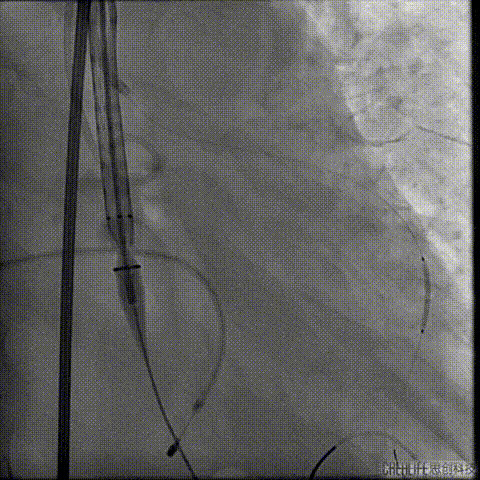

导丝跨瓣及测压

此时患者出现室速 血气提示代谢性酸中毒、高钾血症,予电复率、补碱、补镁、碘氨酮等治疗后恢复窦性心律。

预扩主动脉瓣

左冠血流受到影响

予ECOM支持